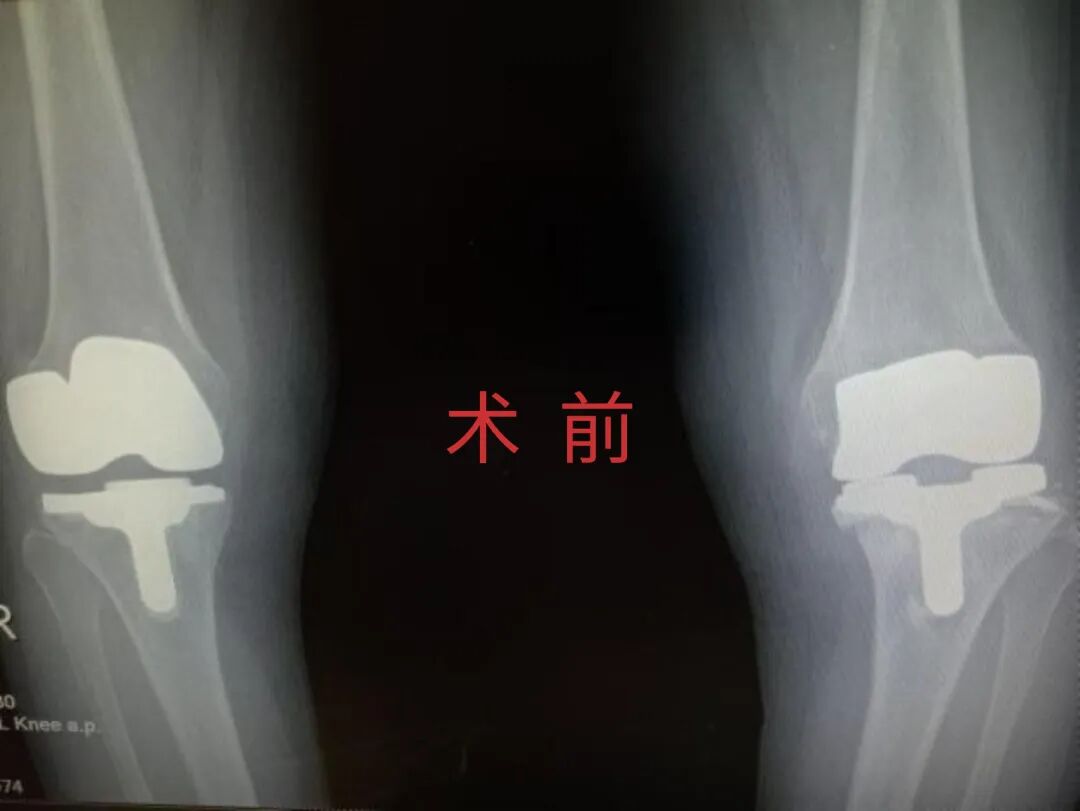

12月17日,贵州航天医院第88次晨读会由我院骨一科主任、副主任医师陈明勇作学术交流,他以“肱骨近端骨折并肩关节脱位的手术治疗”为题,全面讲解了该损伤的手术策略、术中血供保护理念及内侧支撑重建技术等内容,并通过多个典型病例图文资料分享了从损伤机制分析、手术步骤实施到术后随访评估的完整过程与关键细节,为临床处理此类复杂骨折提供了较为全面的技术参考,有助于在手术规划中结合个体情况开展针对性治疗。 贵州航天医院 骨科专家简介 陈明勇 骨一科主任,副主任医师 临床擅长:从事创伤骨科工作约20年,对骨缺损、骨不连、骨肿瘤、肢体畸形等的肢体矫形重建及功能重建,慢性化脓性骨髓炎的根治治疗、糖尿病足的保肢治疗、快速康复理念(ERAS)下的老年骨折的诊治,四肢复杂骨折的诊治,四肢骨折等微创手术治疗具有丰富的临床经验。 2004年毕业于遵义医学院临床专业,曾在中国人民解放军总医院、广西医科大学第一附属医院、上海第六人民医院骨科进修。中国中西医结合学会骨伤科专业委员会横向骨搬移治疗糖尿病足及微血管网再生学组首届委员,遵义市医学会创伤分会常务委员。 瞿 晖 骨科党支部书记,骨二科主任,副主任医师 临床擅长:对骨科的常见病、关节外科、脊柱外科及运动医学疾病的诊治具有丰富的临床经验,熟练掌握骨科手术操作技术。 毕业于遵义医学院临床医学系,2005年前往广州中山大学第一附院骨显微医学部进修学习,2011年前往成都华西医院进修学习,并多次在省内外学习骨科相关知识,是中华医学会骨科分会会员。 赵小锋 中共党员,骨二科副主任,副主任医师 临床擅长:从事骨科临床工作11年,对骨科常见病、多发病诊疗有较为丰富的临床经验,擅长脊柱相关疾病诊断及治疗,尤其是颈、腰、腿疼痛疾病诊断及治疗,擅长胸腰椎骨折微创经皮穿刺内固定术、经皮穿刺椎体成形术、经皮穿刺脊柱内镜下腰椎间盘摘除术、单纯开创腰椎间盘摘除术、腰椎滑脱复位椎间植骨椎融合内固定术、腰椎管狭窄减压融合内固定术及人工髋、膝关节置换术等。 2012年毕业于遵义医学院外科学专业硕士研究生,2019年参加“遵义市115医学人才精英计划”于上海交通大学第一附属医院培训学习,2023年于北京大学第三人民医院脊柱外科进修学习,曾获得遵义市优秀医师荣誉称号。 遵义市手外科第一届委员,遵义市医学会创伤分会第一届委员,遵义市医学会创伤分会第二届委员,贵州省康复医学会第三届脊柱脊髓专业会委员,遵义市医学会烧伤与整形外科学分会委员,发表论文5篇,其中国家级核心期刊1篇,SCI论文1篇,主持市级课题1项并结题,参与市级课题2项。 赵兴东 骨科主任医师 临床擅长:擅长骨科的常见病及各种创伤、四肢骨折创伤修复、骨感染、手足疾病的诊治和手足体表畸形的矫形整复,熟练掌握骨科四肢骨病及创伤的手术操作技术,尤其在四肢关节复杂性损伤、手足外伤、组织缺损创面、难治创面的皮瓣修复方面及平足、高弓足矫形方面及四肢慢性疼痛诊治、康复方面具有丰富的临床经验。 硕士研究生,毕业于遵义医学院临床外科系,2015年前往山东省立医院手足外科进修学习;遵义市医学分会创伤分会第一、二届委员,遵义市手外科医学会第二委届员会常务委员;在省级及省级以上期刊发表文章9篇,参编著作2部,参与主持并完成市级课题1项,参与市级课题2项、省级课题1项。 张艳金 中共党员,骨科副主任医师 临床擅长:从事骨外科工作16年,对复合伤、多发伤的救治、四肢骨干骨折、关节周围骨折、骨肿瘤、骨髓炎等诊治具有丰富的临床经验。 中共党员,硕士研究生,2006年本科毕业于山西医科大学第二临床医学院,2011年研究生毕业于北京军区总医院;在“老年COPD患者合并髋部骨折的诊治”国际合作课题组研究两年,在老年髋部骨折的诊治方面具有丰富的经验,并发表论文6篇;主持遵义市级课题1项,承担遵义医科大学的临床教学工作,获得遵义医科大学优秀带教老师荣誉。编撰有《骨科疾病诊疗精粹》一书,开展2项新技术,编撰地方规范《务川自治县创伤骨科常见疾病诊疗规范》一书。 张俊凯 骨科副主任医师 临床擅长:从事骨科临床工作28年,对创伤骨折、骨感染、骨缺损、骨不连等外科诊治,四肢骨折的微创手术治疗,四肢复杂骨折(如关节内粉碎性骨折、多发骨折等)的损伤控制及手术治疗等具有丰富的临床经验。 1995年毕业于遵义医学院临床专业,2009年前往复旦大学附属医院骨科进修1年。 卢懿明 中共党员,骨科副主任医师 临床擅长:从事骨科工作18年,对创伤骨折、四肢骨折的微创手术治疗、四肢复杂骨折(如关节内粉碎性骨折、多发骨折等)的损伤控制及手术治疗,尤其是髋部骨折的PFNA等微创技术,踝关节骨折、膝关节周围骨折的Mipo微创技术等具有丰富的临床经验,开展了4项新技术,发明6项新型专利技术。 2005年毕业于遵义医学院临床专业,2017年,前往南方医科大学第三附属医院骨科进修半年,回院后运用Mipo技术对骨干骨折及干骺端骨折的治疗技术,同时积极开展骨盆骨折、髋臼骨折腹直肌外侧切口的应用;发表了多篇专业论文,经常参与省内外学术交流会授课,获得医院荣誉称号多个。 邬夏荣 骨科副主任医师 临床擅长:从事骨科工作16年,对四肢复杂骨折、骨肿瘤的诊治,尤其是足踝创伤、慢性踝关节损伤、平足症等诊疗具有丰富的临床经验。 2006年毕业于遵义医科大学临床医学专业,曾在陆军军医大学西南医院进修学习,发表多篇骨科学术论文。 余德怀 中共党员,骨科副主任医师 临床擅长:从事骨科工作10余年,对运动医学、骨关节、脊柱外科常见病、多发病的诊治具有丰富的临床经验。 硕士研究生,2011年毕业于遵义医学院临床医学专业,曾前往遵义医科大学附属医院运动医学专业进修学习;是贵州省医学会运动医学分会青年委员,西部关节镜联盟委员;发表多篇骨科学术论文。 冯 乾 骨科副主任医师 临床擅长:从事骨科工作近20年,熟练掌握骨科多发病及常见病的诊治,尤其对脊柱退变性疾病的诊断及治疗具有丰富的临床经验,主要研究脊柱微创相关治疗方式,能熟练开展椎间孔镜及UBE。 曾前往北京大学第三医院进修学习疼痛及椎间孔镜、首都医科大学友谊医院专业进修脊柱内镜;是贵州省康复医学会第三届脊柱脊髓专业委员会委员;发明专利3项、发表脊柱外科专业论文多篇。 贵州航天医院骨科简介 基本情况 贵州航天医院(原3417医院)骨科组建于1968年,前身是以创伤和断肢(断指)再植闻名于世的上海市第六人民医院骨科,中国断肢(断指)再植的奠基者、中科院院士陈仲伟等专家莅临科室指导医疗和教学,并在70年代开展了贵州省首例断肢(断指)再植手术。组建50余年来,诊治患者已逾百万,挽救了无数的伤病员,成为了保障遵义地区人民群众健康的重要支撑。 经过几代人的不懈努力,今天的骨科,已由创伤骨科发展至骨病、骨肿瘤、骨结核等领域,现有脊柱外科、关节外科、四肢创伤、手足外科四个亚专科,成为了集医疗、教学、科研于一体的综合学科,是贵州省临床重点专科、遵义市临床重点专科、遵义市骨科临床医学中心、遵义市基层骨科专科联盟理事长单位。 科室目前开放床位110张,共有医护人员50余人,副高级以上专家18人,硕士研究生15人。拥有一流骨科医疗设备多台,每年不定期选派优秀技术骨干到全国各大知名医学院校进修、学习、参观、交流,并邀请国内、国外知名专家教授来院进行交流、指导,通过不断引进国内外先进的诊疗技术,科室医疗技术水平稳步提升,为广大人民群众提供了优质的医疗服务。 专科特色 骨一科 (一)骨缺损、骨不连的肢体与功能重建 胫骨横向骨搬移技术治疗糖尿病足: (二)慢性骨髓炎的根治治疗 (三)肢体缺血性疾病如糖尿病足、脉管炎的保肢治疗 (四)皮瓣修复 (五)复杂创伤的治疗 (六)老年髋部骨折及小儿骨折快速手术 老年髋部骨折: 骨二科 (一)胸腰椎骨折微创经皮椎弓根螺钉固定术 (二)老年性骨质疏松性患者腰椎滑脱脊柱内固定术(骨水泥螺钉) (三)V形双通道脊柱内镜技术(VBE)腰椎融合术治疗腰椎退行性疾病 (四)老年性骨质疏松性骨折(PVP/PKP)术 (五)人工髋关节置换术 (六)双侧股骨头坏死人工全髋关节置换 (七)右侧全髋置换术后假体周围骨折翻修 (八)人工膝关节置换术 (九)人工膝关节假体松动翻修 (十)关节镜技术 传统手术切口 关节镜技术切口 诊疗范围 骨一科 1.四肢创伤、矫形。 2.手、足踝外科。 骨二科 end